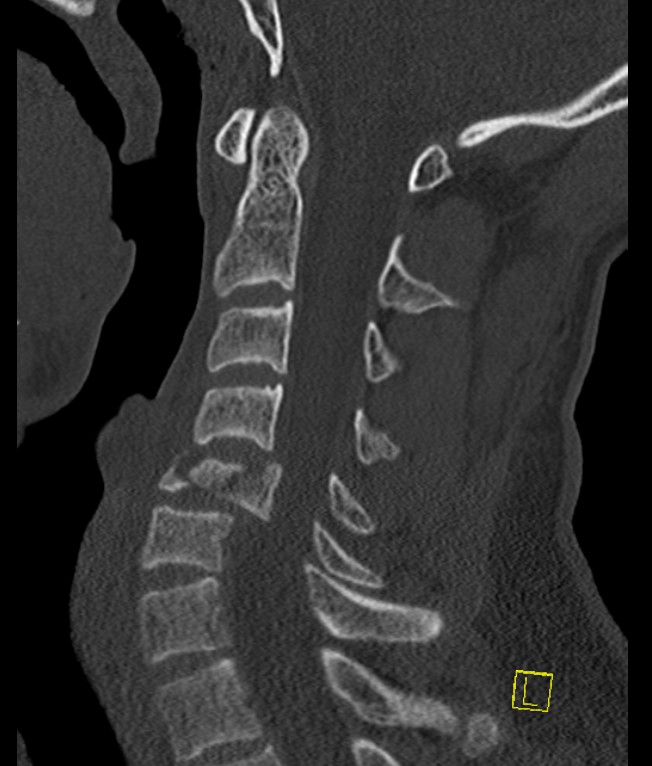

CT

Canal compromise / neurological injury

- retropulsed fragments

- typically one or two main retropulsed fragments

Anterior & middle columns fail

- if severe, posterior ligament complex fails